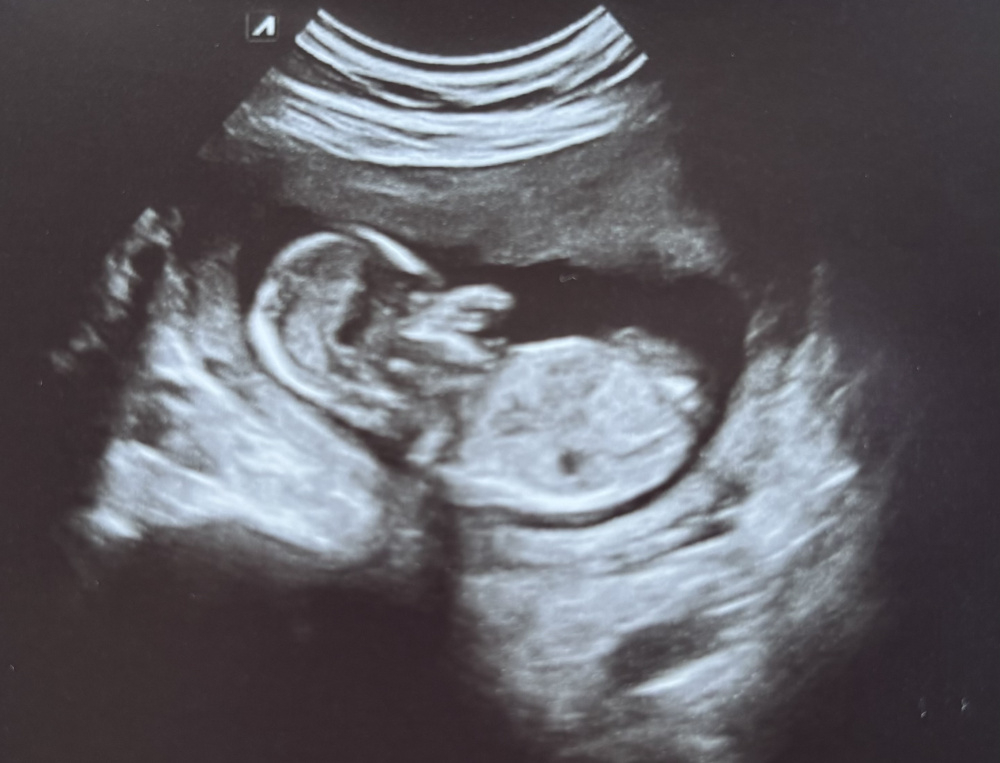

Ausserdem kann man an diesem bild bicht so viel erkennen, seitlich oder von unten wäre einfacher um das ganze nochmal zu bestätigen